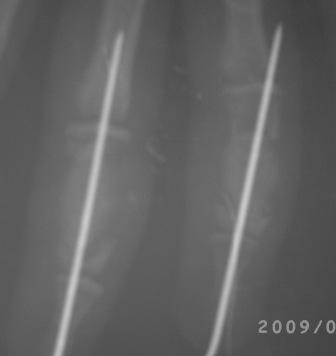

20.03.09г. операция. Экскохлеация не получилось, стенки диафиза фаланги как папиросная бумага, хотел сохранить хоть одну стенку, но и это не получилось - ломается и крошится, удалось сохранить оба эпифиза, проксимально чуть стенку и метафиза. В полости белесоватая кашицеобразная масса. Дефект заполнен сформированной под фалангу аутопластикой из гребня подвздошной кости, сверху ушита надкостницей, пальцевые сосуды сохранены. Материал отправлен на гистологию. Фикация спицей трансартикулярно, вынужденно фиксировали оба сустава - но это мне никак не нравится!

Уважаемые коллеги, помогите! Как лучше фиксировать, чтобы освободить суставы, или хотя бы быстрее восстановить движения! Девочка очень просит, чтобы работали пальцы, тем более что это правая рука!

Послеоперационные x-ray некачественные, всё ж кое что можно разглядеть, постараюсь повторно снять!

Стояние довольно приличное. Хорошо, что сохранили суставы. В такой ситуации вообще-то ничего и не придумаешь, кроме спиц. Поэтому я бы не менял метода фиксации. По снимкам больше похоже было на энхондрому, но вот меня смущает белесоватый цвет содержимого и кашицеобразная консистенция. Подождем гистологии.

Подбор спиц в данном случае - не очень удачный, Абдуашид, извините, я говорю что думаю, осевая "фиксация" типа шашлык на некровоснабжаемом аутоостеотр-те не надежна, думай, исходя из ситуации.